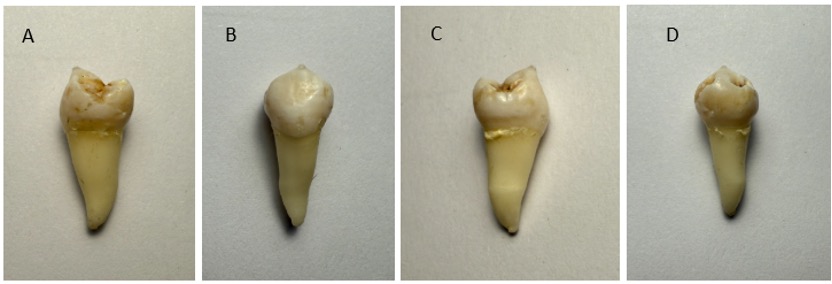

After extraction, the tooth was scanned using an intraoral scanner (iTero IOS). This ex vivo scanning method provides a reference model without in vivo imaging artifacts. ⁷, ¹⁵

Figure 2. High-resolution optical scans of an extracted mandibular premolar (45) captured at 90-degree rotations along the long axis (root-crown) of the tooth. The STL model shown below is compared to the view of the extracted tooth in image C.